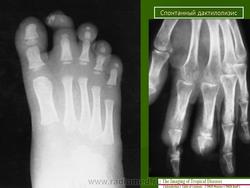

Аингум (ainhum) - спонтанный дактилолизис, описал Da Silva Lima (1852,1867).

Клиника аингума проявляется в виде кольцевидной перетяжки различной ширины с явлениями склероза преимущественно в области пятых пальцев стоп, иногда кистей. В результате дегенерации жировой и фиброзной тканей, постепенного рассасывания кости через 3-5 лет происходит спонтанная безболезненная ампутация пальца.